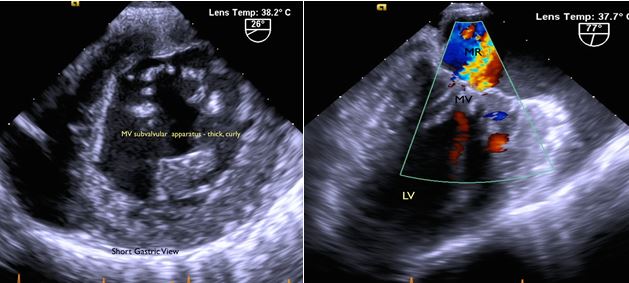

Fig. 3A: Mitral valve leaflet: thickened, redundant. Moderate central regurgitation. Subvalvular apparatus: nodular, thickened, fused.

Fig. 3B: Aortic Valve: thickened, nodular, calcified valve. Severe AS and mild AI.